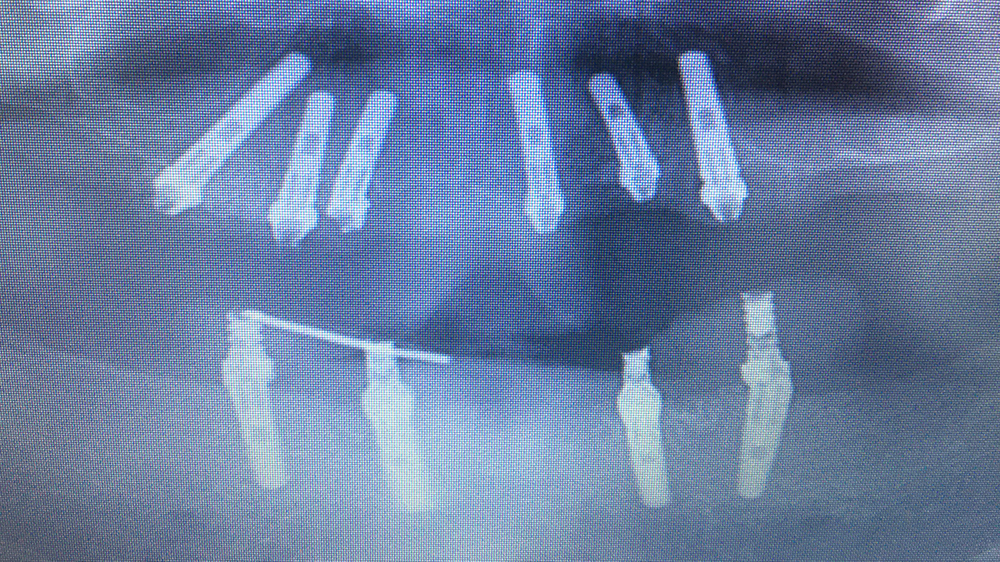

症例2

Before

After

WYさん 60代女性

非喫煙者、重度歯周病

治療の期間・回数:一度目:上下とも約6か月/オールオン4:5か月

​治療の価格:一度目:上の歯1,600,000円、下の歯700,000円

オールオン4:1,600,000円

治療内容:この方は40代で重度の歯周病になり、多くの歯を失いました。

20年前に、上あごには4本のインプラントを入れましたが、骨が少なかったため、手術中に骨が割れるトラブルがありました。そのため、4か月間待ってから仮の歯を入れました。

下あごは残っている歯を使ってブリッジを作りました。最終的には上下とも、金属の土台にセラミックを貼った「メタルボンド」の歯を入れています。

その後、下あごのブリッジは10年も持ちましたが、最終的には全ての歯を失いました。そこで韓国製オステムのインプラントで「オールオン4」という方法で再建しました。手術当日に仮の歯を入れ、最終的にはスクリューで固定するメタルボンドの歯を入れています。

重度の歯周病で骨も少ない条件でしたが、上あごのインプラントは19年間安定して使えています。